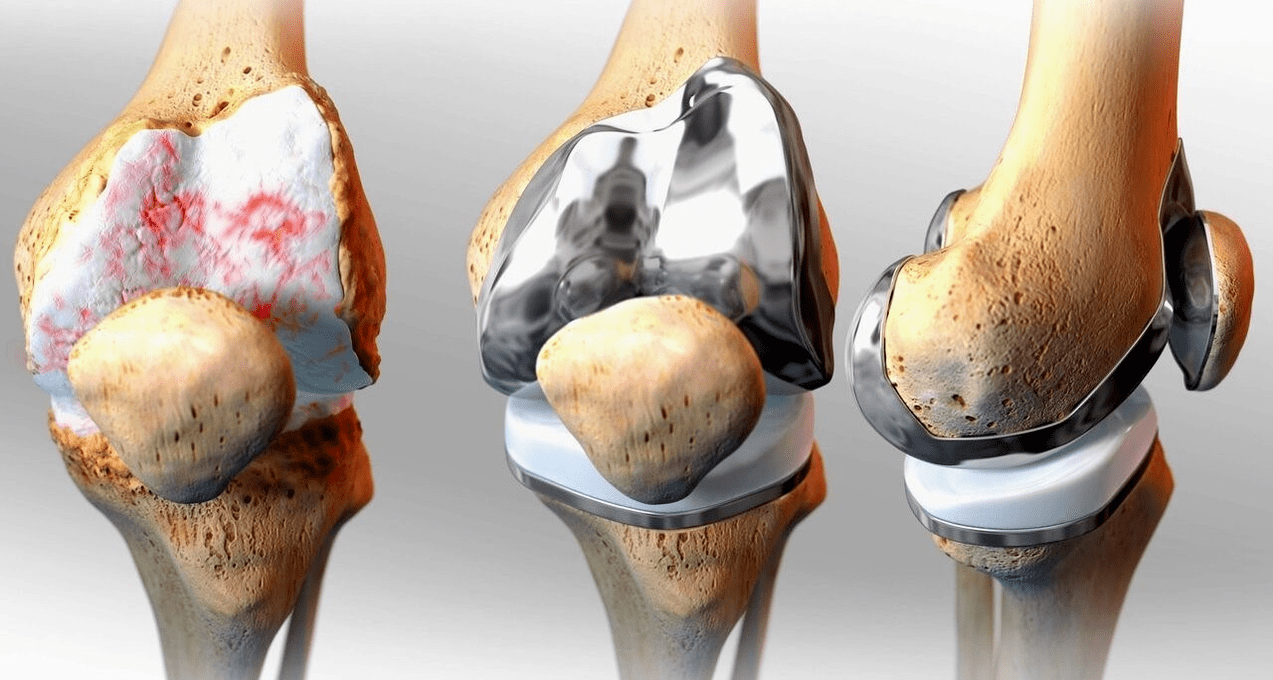

Χειρουργική θεραπεία και ενδοπροσθετική

Η αντικατάσταση της ενδοπρόσθεσης είναι μια κοινή και αποτελεσματική χειρουργική μέθοδος για τη θεραπεία της σοβαρής γονάρθρωσης, η οποία σας επιτρέπει να διατηρήσετε την κινητικότητα των άκρων και την ικανότητα να ζήσετε μια πλήρη ζωή στη συνέχεια. Πρόκειται για μια επέμβαση υψηλής τεχνολογίας που διαρκεί περίπου μιάμιση ώρα. Στην μετεγχειρητική περίοδο είναι απαραίτητη η μακροχρόνια αποκατάσταση και ανάπτυξη της άρθρωσης. Μετά από 25-30 χρόνια, όταν η τεχνητή άρθρωση φθαρεί, χρειάζεται και πάλι αντικατάσταση.

αντικατάσταση γόνατος